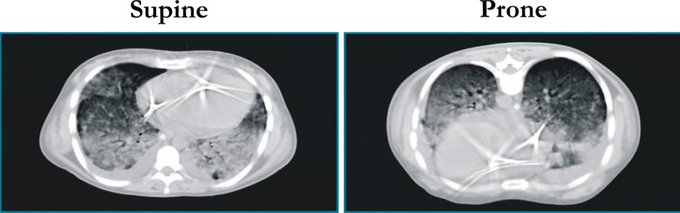

ncbi.nlm.nih.gov/pubmed/23688302

(5) That all sounds great, but how does prone positioning improve oxygenation? Well, a few theories exist:

(6) First, let’s look at redistribution of blood flow. Studies in animals and humans (using PET) have shown that blood flow distribution in the lung does not change substantially from supine to prone position in ARDS.

(8) Which leads us to our third theory: more uniform alveolar inflation! Anatomically speaking, lung mass is greater in the dorsal regions than the ventral regions.

(9) When supine, there is greater distension of the ventral lung regions due to gravity, as well as poor “shape matching” between the lung and chest wall (think of a cone inside a cylinder).

(10) When prone, the forces of gravity and “shape matching” oppose each other, which leads to more homogenous inflation of the pulmonary units from the sternum to vertebra.

(11) Additionally, the heart weight no longer compresses the left lower lobe and abdominal pressure is lessened.

(12) This leads to an overall recruitment in (larger) dorsal lung regions which outweighs the degree of de-recruitment in the (smaller) ventral lung regions, leading to an overall increase in lung compliance.